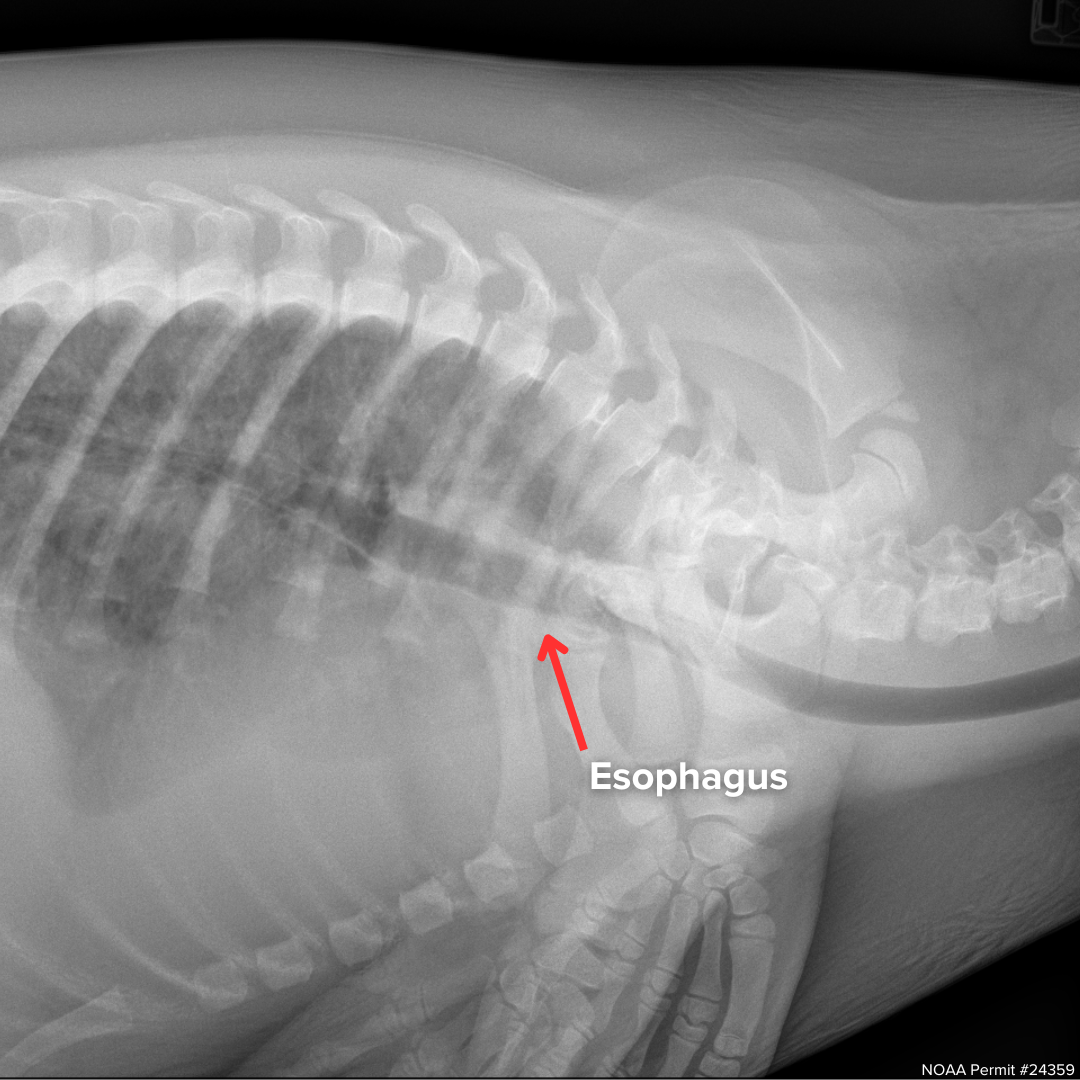

On June 3rd, he was given another examination, this time with x-rays as one of the added procedures, and the images that came back were not promising. Griffin had a condition called megaesophagus.

An x-ray of Griffin from June, with the red arrow pointing to his enlarged esophagus visible through his ribs and spine.

An x-ray of Griffin from October, with the red arrow pointing to his resolved esophagus.

“Fortunately, with continued supportive care, Griffin's bloating resolved and he was able to swim and forage like a normal seal," said Michelle. At the beginning of October, when he reached his release weight of 50 pounds, he was imaged a second time, and it was confirmed that Griffin’s esophagus had returned to a normal size.